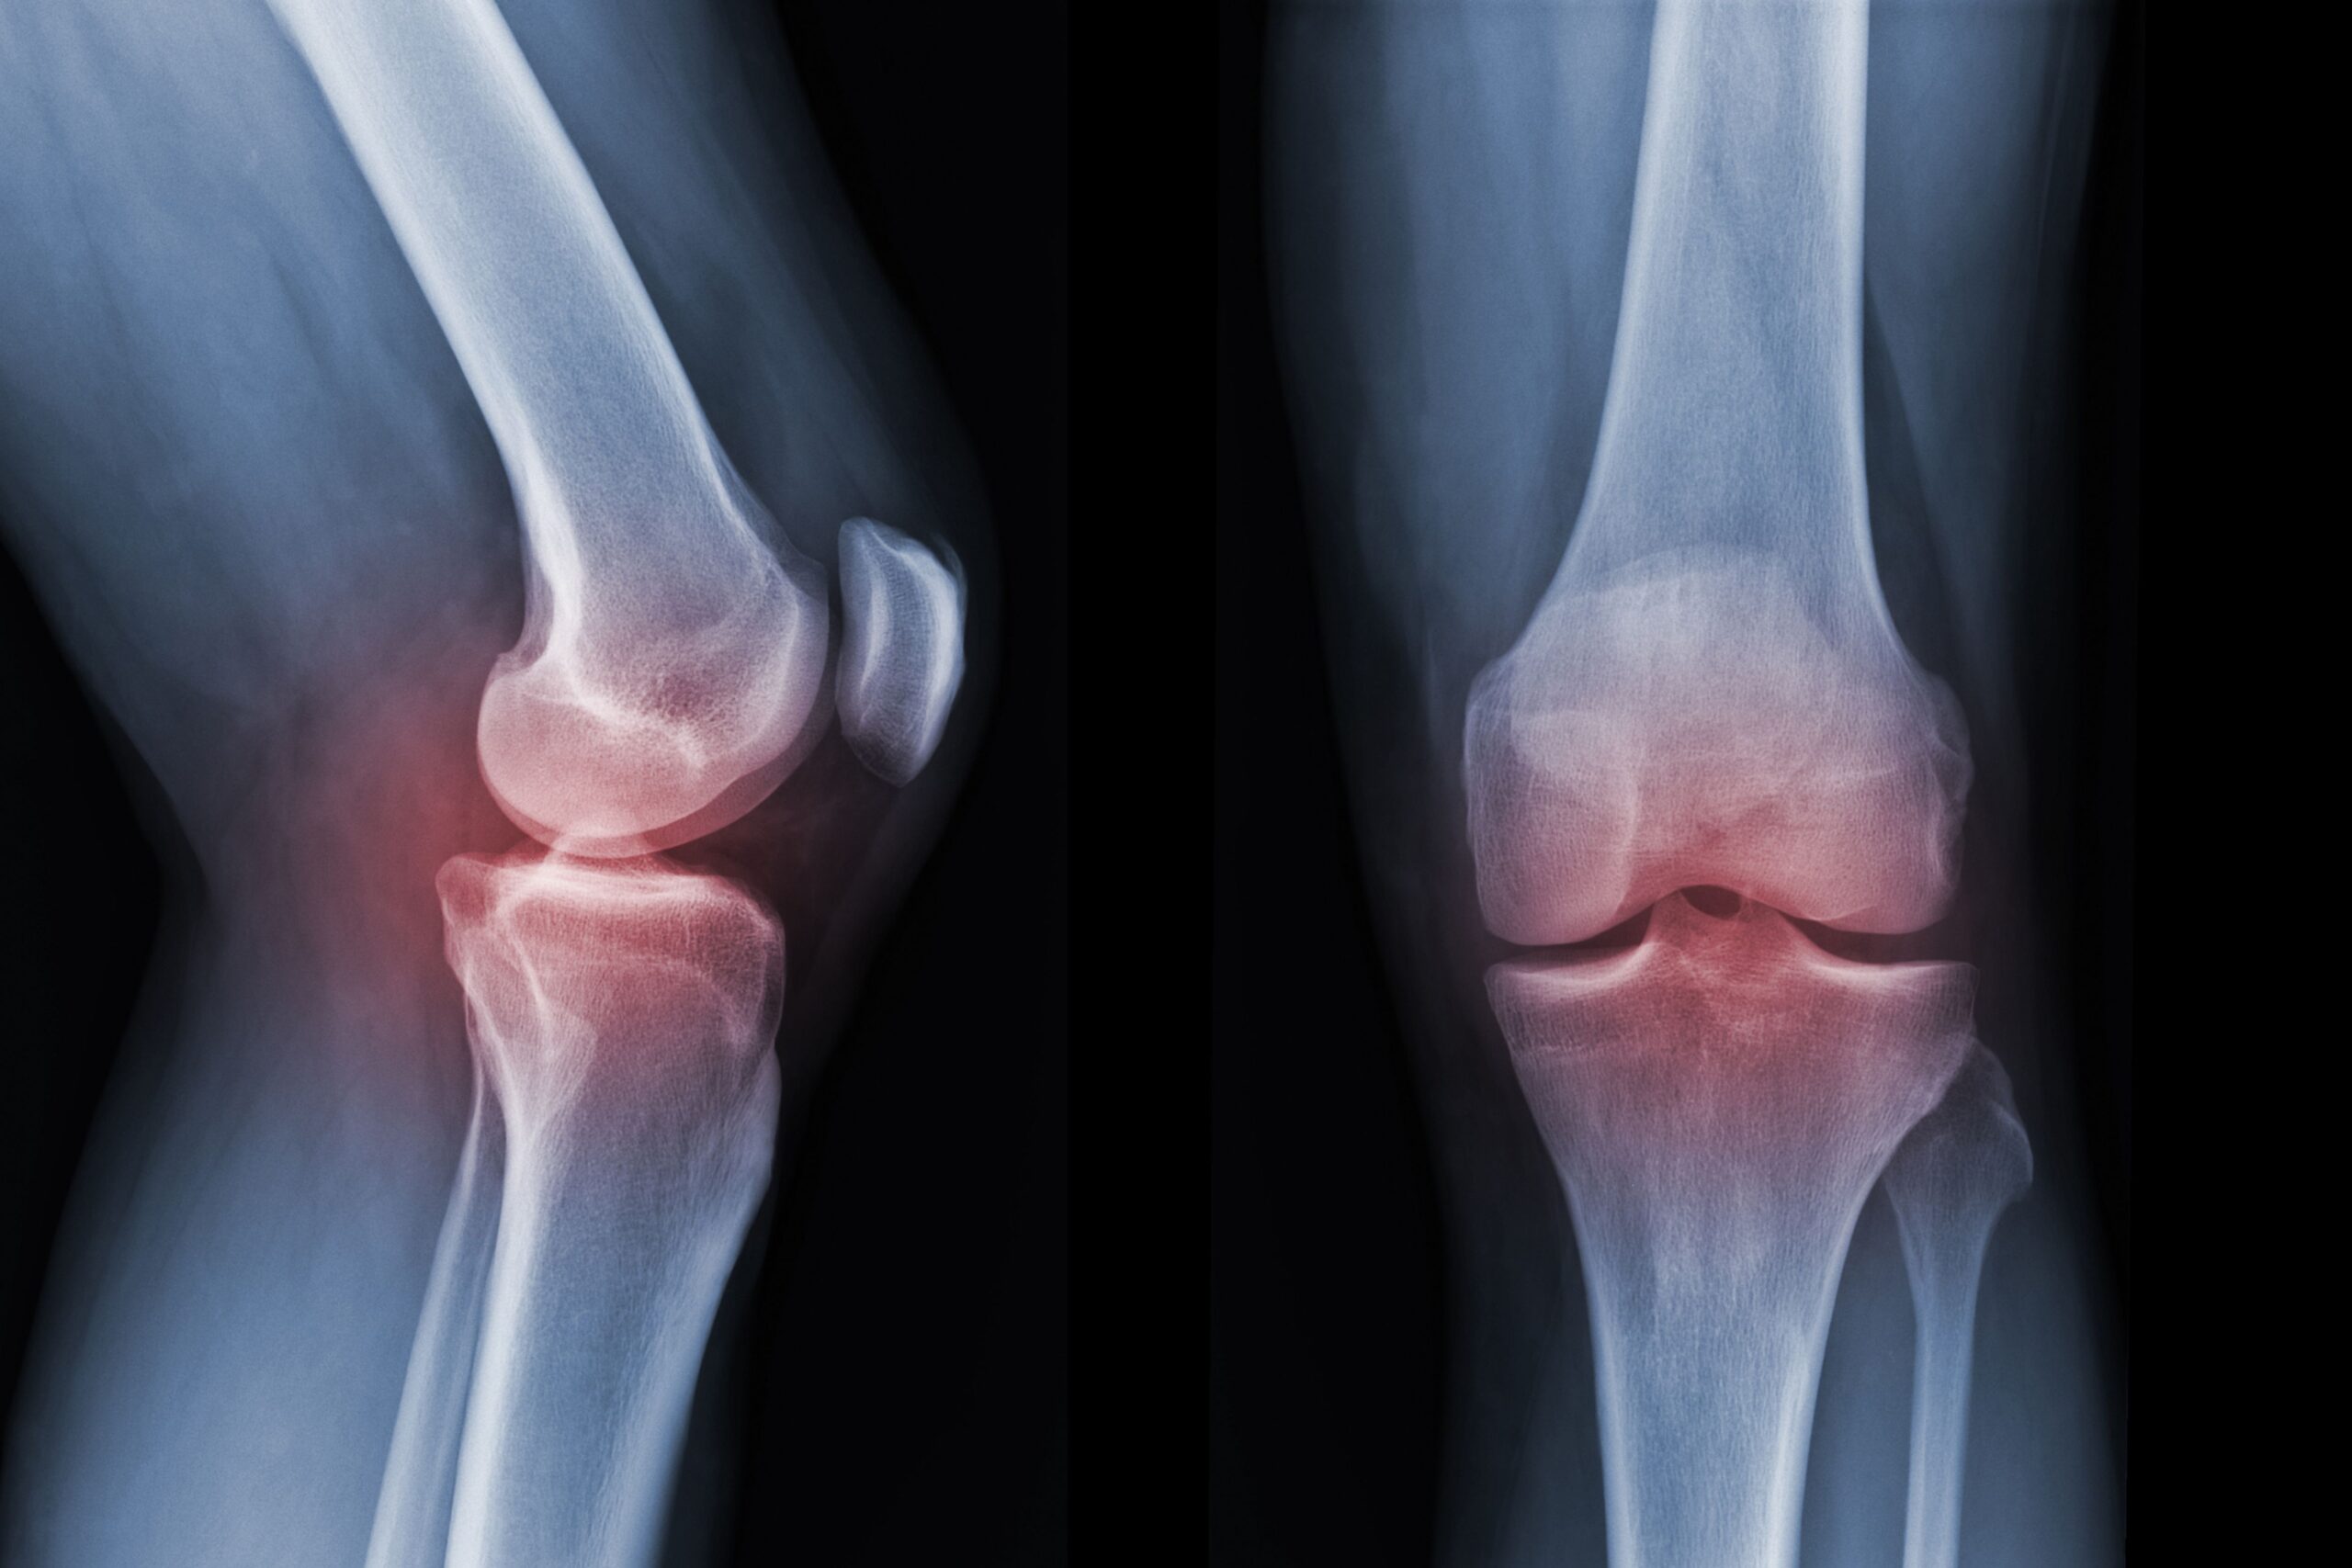

Tra le strategie attualmente studiate per il trattamento dell’artrosi di ginocchio c’è la medicina rigenerativa, che vorrebbe ridurre lo stato infiammatorio articolare e rallentare il progredire della patologia, se non addirittura ristabilire la salute articolare. Se normalmente si parla di plasma ricco di piastrine (PRP, platelet rich plasma) e cellule staminali, una recente revisione narrativa si concentra sugli esosomi, nanovescicole che trasportano proteine, lipidi e acidi nucleici e che rivestono un ruolo essenziale nella comunicazione tra cellule, nella immunomodulazione e nella riparazione dei tessuti.

Un primo aspetto preso in considerazione dagli autori della revisione è la possibile funzione diagnostica degli esosomi. Nella cellula, gli esosomi rivestono un ruolo fondamentale nei processi patologici, dal momento che contribuiscono alla regolazione dei processi infiammatori. Non solo. Per questa ragione, gli autori evidenziano come in diversi studi presenti in letteratura gli esosomi sono indicati come possibili marker di patologia. Ciò vale soprattutto negli stati precoci dell’artrosi di ginocchio, ancora esenti da sintomi quale il dolore e la disfunzionalità articolare e da segni di danno cartilagineo nelle immagini mediche.

Un altro possibile marcatore, trasportato dagli esosomi, è il micro-RNA 140, la cui espressione aberrante può indicare un’azione condroprotettiva e, quindi, un processo patologico a carico delle cartilagini. Una diagnosi precoce, effettuata prima che vi sia un reale danno a carico delle cartilagini del ginocchio, permetterebbe di giocare di prevenzione e di mettere in atto cure davvero efficaci nel contrastare questa patologia articolare, sempre più diffusa nella popolazione.